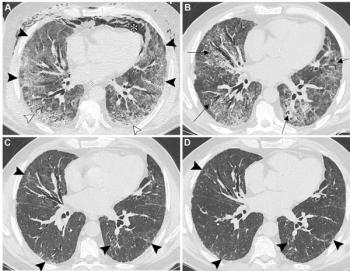

Developed by 21 thoracic radiologists, the new international consensus statement addresses appropriate indications, scan acquisition and keys to reporting for the use of chest CT imaging in evaluating for residual lung abnormalities from COVID-19.

In a prospective study involving nearly 100 patients with Long Covid, 57 percent of patients had PET/MRI abnormalities and 90 percent of the cohort had abnormalities on dual-energy CT scans.